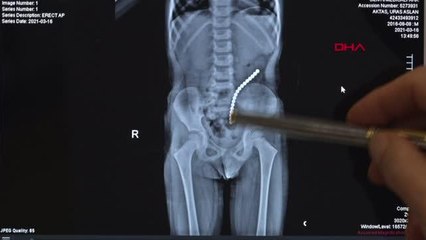

İstanbul'da yaşayan 4 yaşındaki Uras Aslan Aktaş, şiddetli karın ağrısı şikayetiyle ailesi tarafından hastaneye götürüldü. Çekilen röntgen filmi sonucu küçük çocuğun bağırsağında tam 19 tane 'neodyum mıknatıs' tespit edildi. Ameliyata alınan minik çocuk, 45 dakikalık operasyon sonrası sağlığına kavuştu. brpUras Aslan Aktaş, şiddetli karın ağrısı ve kusma şikayeti sonrası ailesi tarafından hastaneye kaldırıldı. Yapılan tetkiklerde küçük çocuğun bağırsağında tam 19 tane oyun amaçlı kullanılan neodyum mıknatıs tespit edildi. p"ŞİDDETLİ KARIN AĞRISI YAŞADI"pBağırsağını delen cismi fark eden Çocuk Cerrahisi Uzmanı Prof. Dr. Ali Çay çocuğu ameliyata aldı. 45 dakika süren operasyonda tam 19 tane mıknatıs çıkarıldı. Şaşkın olduğunu söyleyen anne Ayşegül Aktaş, "Kahvaltı esnasında çok şiddetli karın ağrısı oldu. Ben tuvalete gitmesini istedim. Ama ağrısı devam etti. Sonra dinlenmesi için yatak odasına götürdüm o esnada bana 'anne ben mıknatıs yuttum' dedi.